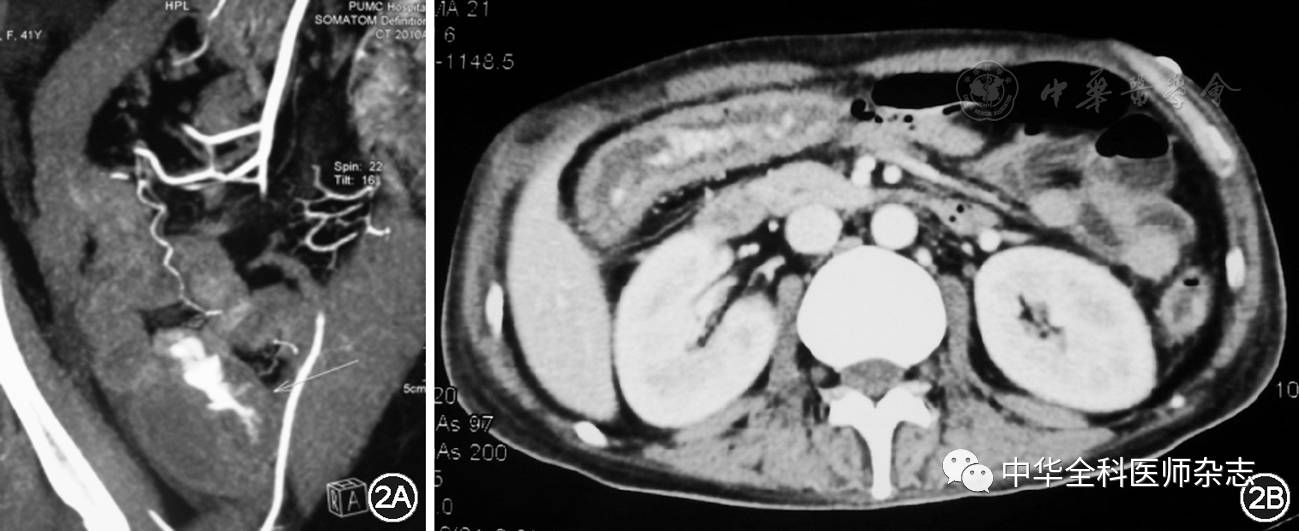

多层螺旋CT血管成像(multidetector computed tomography angiography, MDCTA)是近年来LGIB诊断技术的重要进展。MDCTA较常规CT明显提高了扫描速度,可获得高分辨率的薄层轴位图像,适合显示肠道病变。通过外周静脉(通常是肘静脉)以较高速度(4 ml/s)注入造影剂,在动脉期及门脉期若发现造影剂溢入结直肠,则提示活动性LGIB(图2)[14]。文献报告MDCTA可检出0.3 ml/min的急性LGIB[3]。检查前应避免应用口服对比剂,以免干扰对肠腔内积血的判断。北京协和医院的一项前瞻性研究发现,MDCTA诊断活动性消化道出血的敏感性为86.0%,特异性为100.0%,阳性预测值100.0%,阴性预测值60.6%,准确率88.5%[15]。荟萃分析表明,MDCTA对活动性消化道出血的总体敏感性为85.2%,特异性为92.1%,受试者工作曲线下面积为0.935,基本可以取代传统血管造影的诊断作用[16]。MDCTA诊断活动性LGIB具有简单、快速、无创等优势,并且可显示病变形态学特征以指导后续治疗,但也存在射线暴露、造影剂过敏、肾功能损害等不良反应,临床应予注意。

图2 CT血管造影在急性下消化道出血的应用。图2A:女性,41岁,血便伴发热,多层螺旋CT血管成像显示盲肠造影剂外溢入肠腔,经手术确诊为克罗恩病 图2B:男性,40岁,脓血便8周。住院期间突发大量鲜血便,多层螺旋CT血管成像显示横结肠造影剂外溢,诊断重度溃疡性结肠炎合并巨细胞病毒肠炎